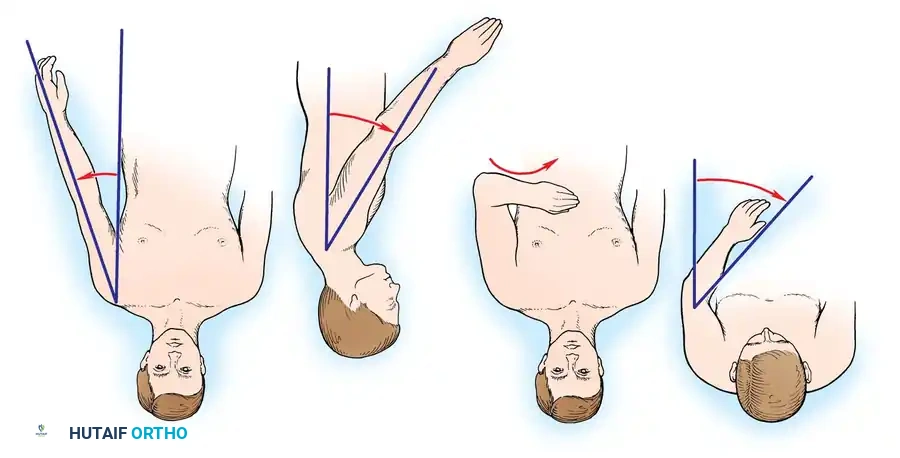

Historically, the optimal position has been a subject of intense debate. In 1974, Rowe recognized the severe disadvantages of excessive abduction and flexion, which lead to scapular winging at rest and muscle fatigue. Rowe recommended a position of 20 degrees of abduction, 30 degrees of forward flexion, and 40 to 50 degrees of internal rotation.

Subsequent functional analyses by Hawkins and Neer refined these parameters. They identified a range of acceptable positions, recommending 25 to 40 degrees of abduction, 20 to 30 degrees of flexion, and 25 to 30 degrees of internal rotation.

Cofield and Briggs, in a study of 71 shoulder arthrodeses, concluded that the degree of internal rotation is the single most important factor in determining functional success. Insufficient internal rotation prevents the patient from reaching their midline, face, or contralateral shoulder. Groh et al. defined symptomatic malunion requiring corrective osteotomy as greater than 15 degrees of flexion, and rotation of less than 40 degrees or more than 60 degrees.

Because radiographic measurement of these angles intraoperatively can be challenging due to patient positioning, clinical landmarks are heavily relied upon.

1. Abduction: Measured clinically as the angle formed between the medial border of the humerus and the lateral border of the trunk.

2. Flexion: Determined by observing the angle the humerus forms with the horizontal plane of the thorax.

3. Internal Rotation (The Hand-to-Mouth Test): With the shoulder provisionally fixed in the desired abduction and flexion, the elbow is flexed to 90 degrees. The hand should rest comfortably over the ipsilateral chest, midway between the sternum and the axilla. Further flexion of the elbow should allow the tip of the thumb to easily reach the patient's chin and mouth.